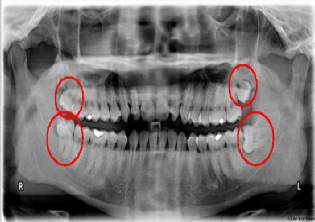

Ο φρονιμίτης ή σωφρονιστήρας ή τρίτος γομφίος αποτελεί το τελευταίο προς τα πίσω δόντι της μόνιμης οδοντοφυΐας. Οι φρονιμίτες ανατέλλουν φυσιολογικά συνήθως στην ηλικία των 17-23 ετών, αν και ορισμένες φορές δεν ανατέλλουν καθόλου και παραμένουν έγκλειστοι ή ημιέγκλειστοι  λόγω έλλειψης χώρου για την ανατολή τους.Ανάλογα με τη θέση που βρίσκονται, είναι και τα προβλήματα που δημιουργούν.

Το συνηθέστερο πρόβλημα με τους έγκλειστους φρονιμίτες είναι ότι προκαλούν φλεγμονές. Σε ορισμένες μάλιστα περιπτώσεις, λόγω κλίσης του δοντιού και έντονης επαφής με τον τραπεζίτη που βρίσκεται ακριβώς μπροστά του, προκαλούν μόνιμη καταστροφή του οστού που στηρίζει τον δεύτερο γομφίο, με αποτέλεσμα την δημιουργία περιοδοντικού προβλήματος.

Ένας φρονιμίτης  που έχει ανατείλει μερικώς, φαίνεται δηλαδή τμήμα της μύλης του αλλά δεν έχει ανατείλει πλήρως, λέγεται ημιέγκλειστος. Ο ημιέγκλειστος φρονιμήτης εμφανίζει συνήθως περισσότερα προβλήματα, καθώς τερηδονίζεται πιο εύκολα από κάθε άλλο δόντι καθώς είναι δύσκολο να καθαριστεί σωστά.

Λόγω της έλλειψης χώρου δεν μπορεί να γίνει καλή στοματική υγιεινή και εγκλωβίζονται μικροοργανισμοί και υπολείμματα τροφών ανάμεσα στο δόντι και στο ούλο, με αποτέλεσμα ην δημιουργία φλεγμονής, που ονομάζεται περιστεφανίτιδα.

Είναι σημαντικό η χειρουργική αφαίρεση των φρονιμιτών να γίνει σε νεαρή ηλικία. όπου δεν θα έχει ολοκληρωθεί η ανάπτυξη των ριζών (που σημαίνει πιο εύκολη, συντηρητική επέμβαση), αλλά – και το πιο σημαντικό – διότι δεν θα έχουν προλάβει να προκαλέσουν μόνιμες βλάβες στα παρακείμενα δόντια και ιστούς.